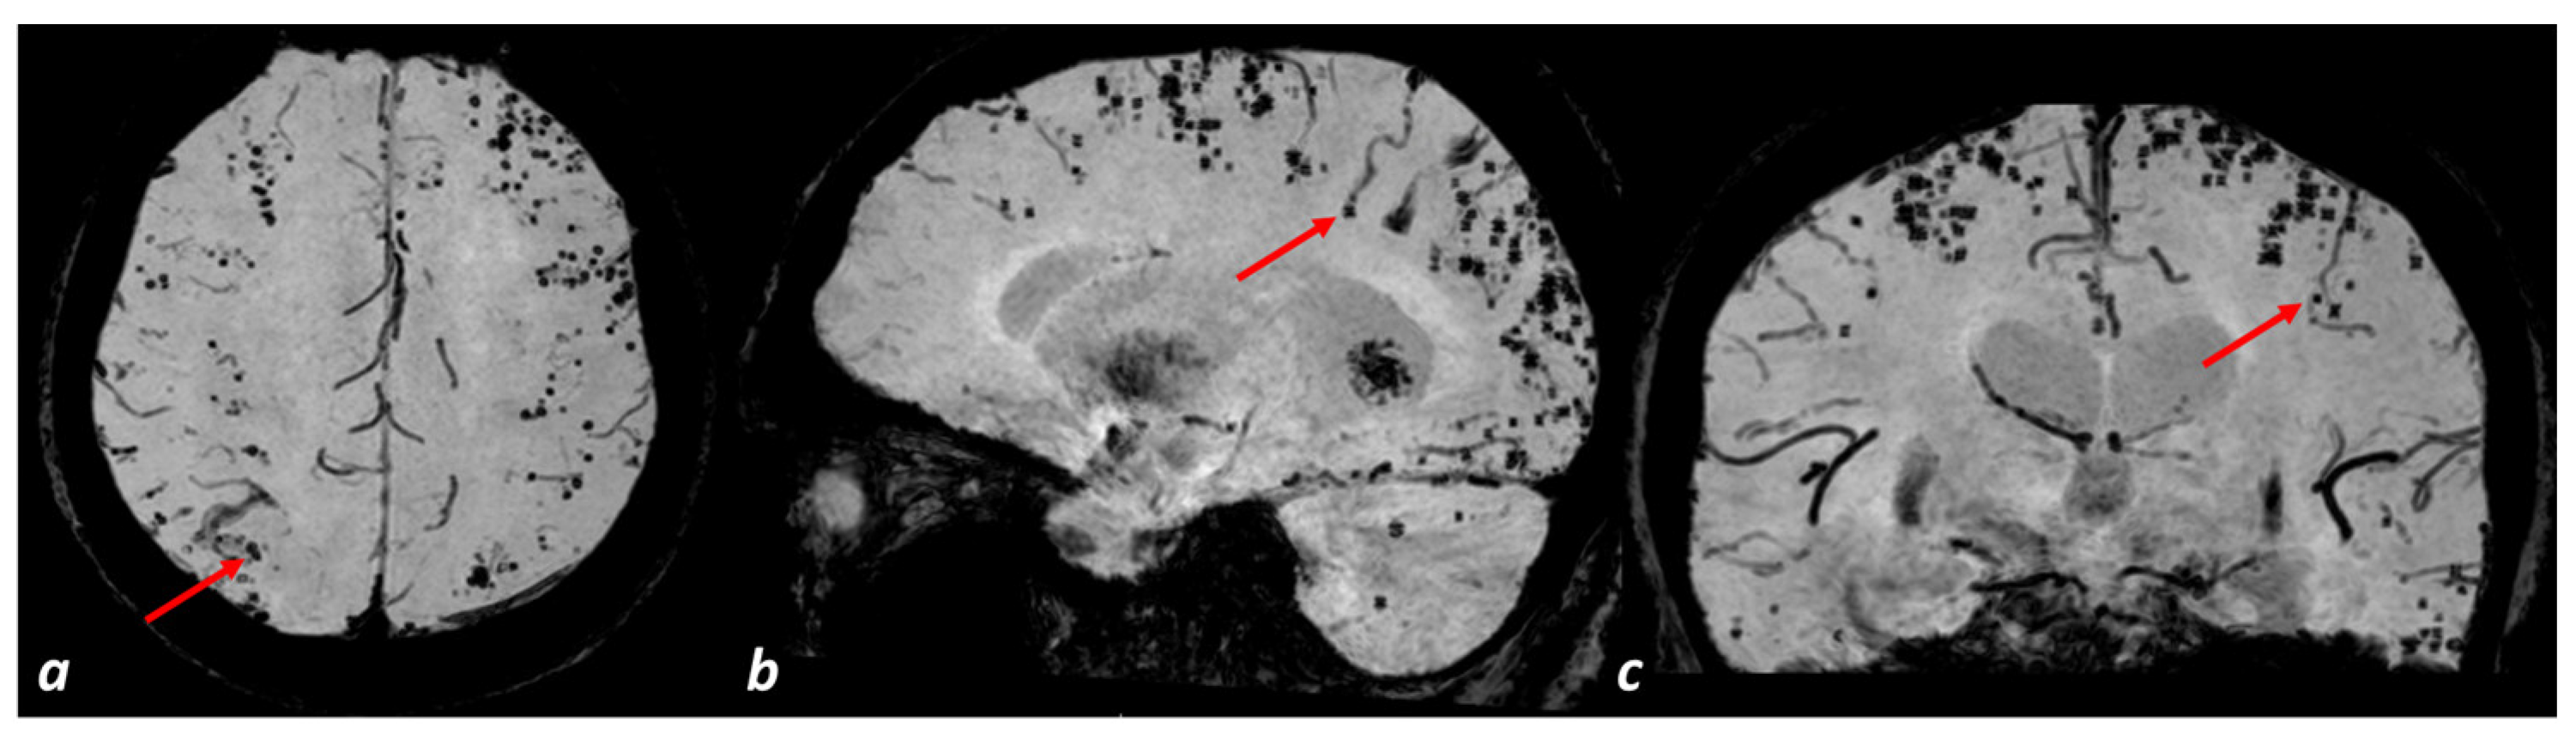

4.1. General Organization of the Cortical Angioarchitecture in Humans: The Arterial Side

6. Potential Contribution of the Venular Involvement to Neuroimaging Markers of CAA

6.3. Microbleeds